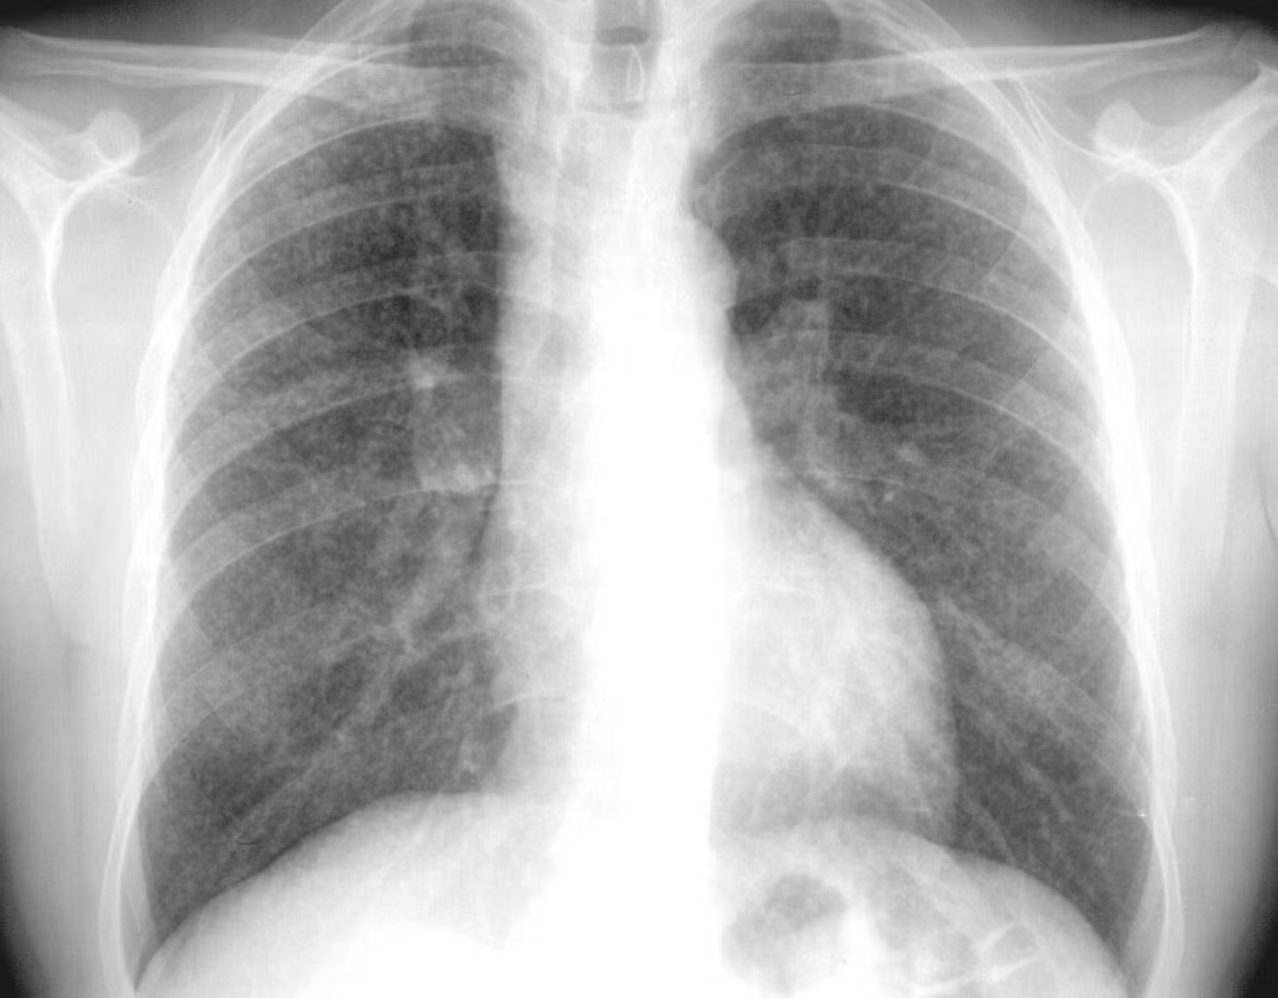

La silicosis es una enfermedad pulmonar rara e irreversible, a menudo mortal, cuya única causa conocida es la inhalación de polvo de sílice. La enfermedad comienza con inflamación y cicatrización de los pulmones, pero con el tiempo puede derivar en insuficiencia pulmonar.

Silicosis: La silicosis es una enfermedad pulmonar crónica e incurable causada por la inhalación de polvo de sílice, que provoca cicatrización pulmonar (fibrosis). Los síntomas incluyen tos persistente y dificultad para respirar que empeoran con el tiempo. Los factores de riesgo son las ocupaciones que implican exposición al polvo de sílice, como la minería, la construcción y el chorro de arena. No existe cura para la silicosis, y el tratamiento se centra en el control de los síntomas y la prevención.

Fibrosis Masiva Progresiva (FMP): La FMP en los pulmones se refiere a la cicatrización grave y la formación de grandes masas debido a la inhalación de polvo (como carbón o sílice), lo que causa dificultad para respirar, tos y mucosidad oscura, provocando una disfunción pulmonar importante y, a menudo, complicando la neumoconiosis de los mineros del carbón o la silicosis.